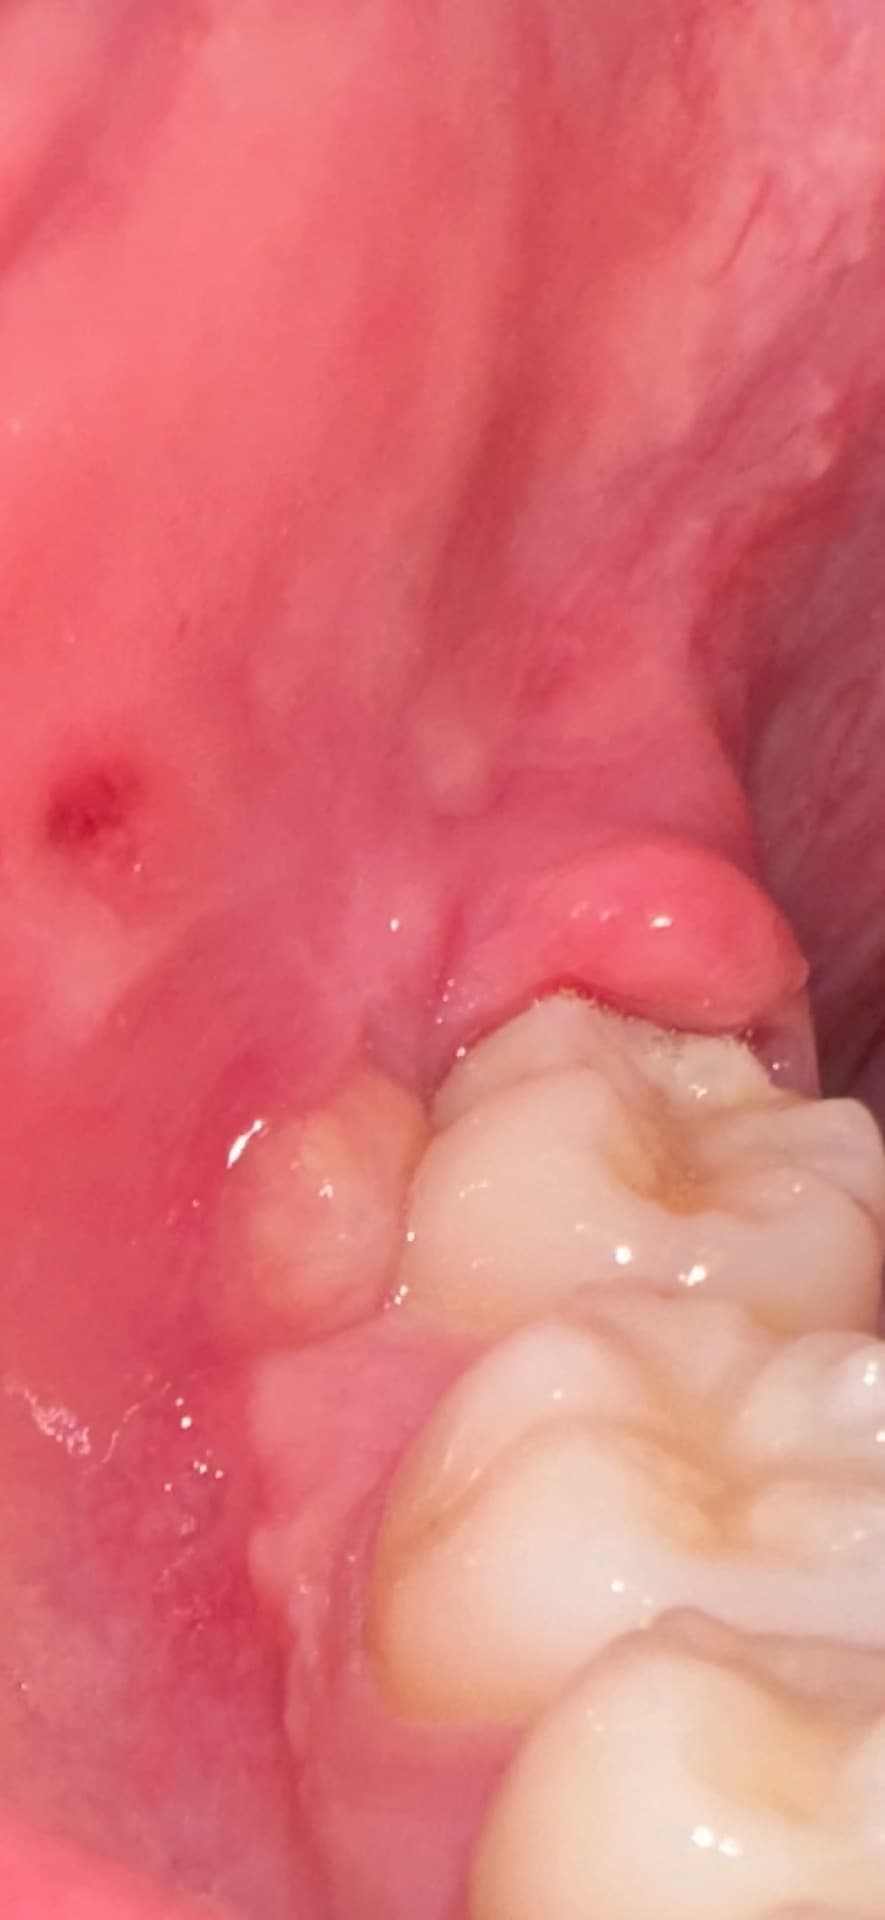

두 달전에 오른쪽 아래 사랑니 뽑았는데요.

화요일부터 사진처럼 염증이 너무 심해가지고

진통제 먹고 버텼는데 오늘은 오한에 열이 너무 심합니다. 염증하나로 이럴 수가 있나요? 귀도 아프고 목도 아프고 턱도 아프고 열나니까 제정신이아닌거갓타요

사랑니를 발치한 부위에 이물질이 들어가게 되면 해당부위가 감염이 되면서 붓고 염증반응이 나타날수 있습니다.